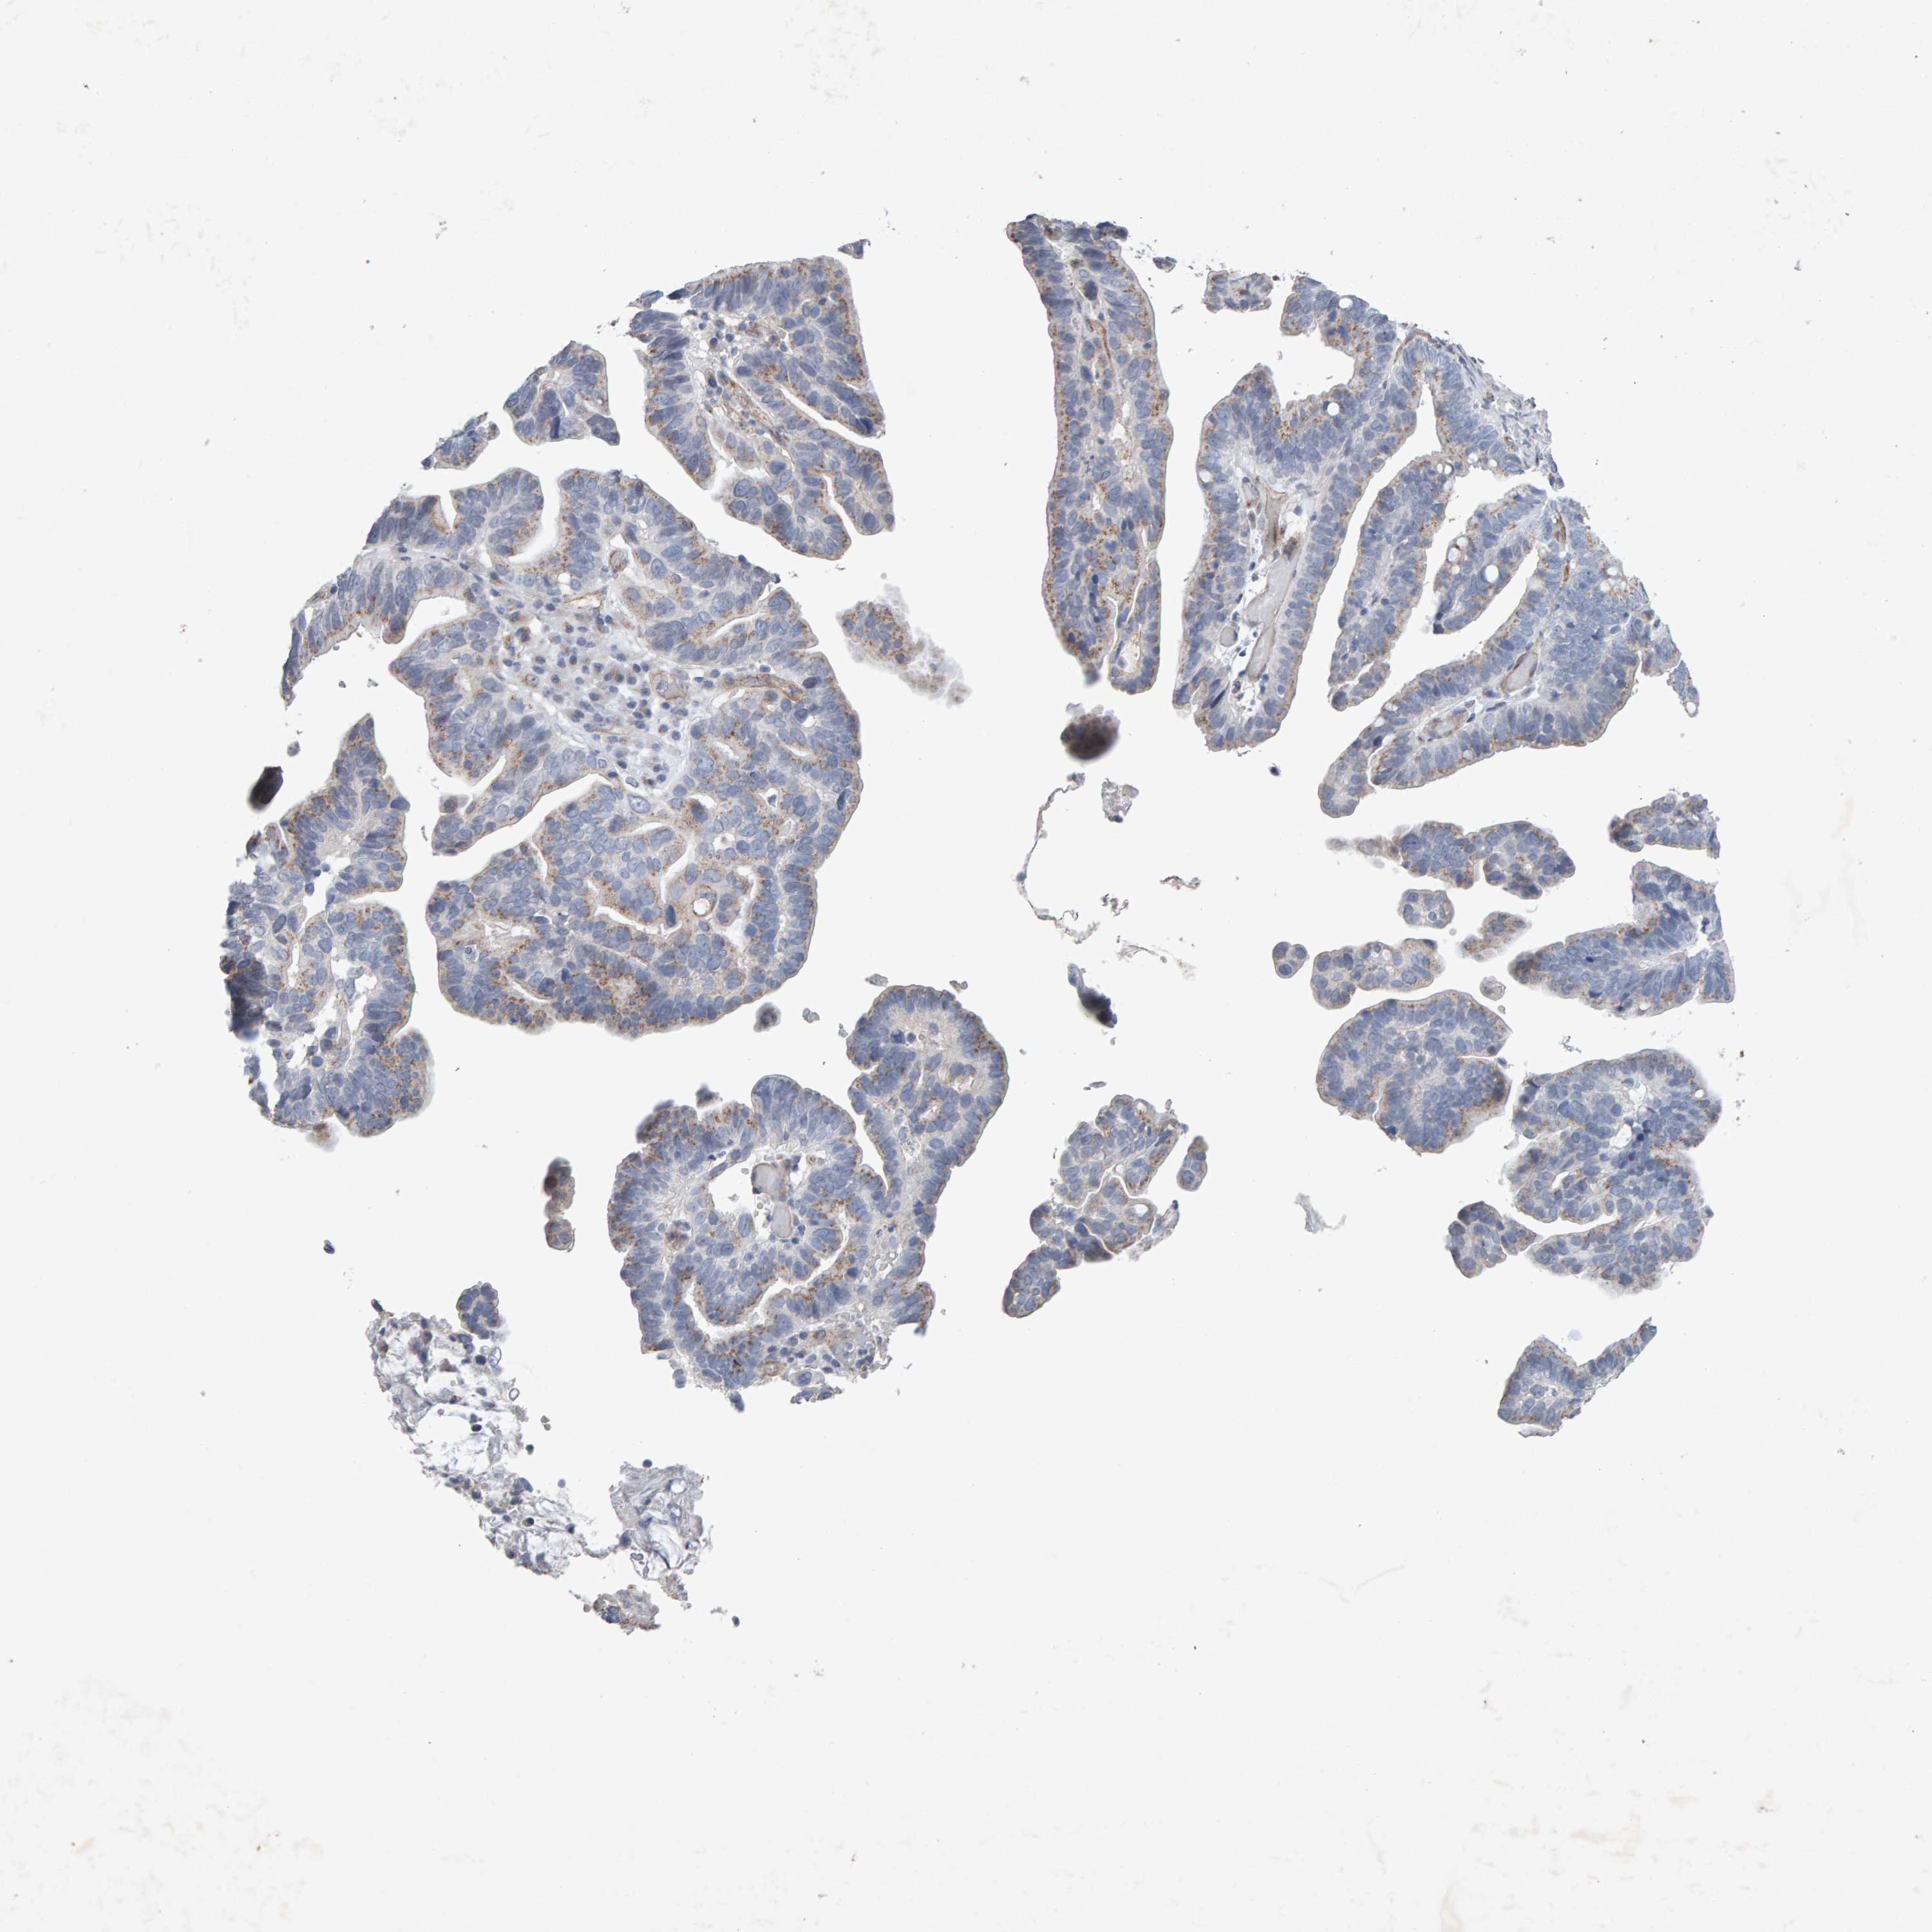

OVARIAN CANCER - Protein expressioni

A mouse-over function shows sample information and annotation data. Click on an image to view it in a full screen mode. Samples can be filtered based on level of antibody staining by selecting one or several of the following categories: high, medium, low and not detected. The assay and annotation is described here.

Note that samples used for immunohistochemistry by the Human Protein Atlas do not correspond to samples in the TCGA dataset.

Antibody stainingi

Antibody staining in the annotated cell types in the current human tissue is reported as not detected, low, medium, or high, based on conventional immunohistochemistry profiling in selected tissues. This score is based on the combination of the staining intensity and fraction of stained cells.

Each image is clickable and will lead to virtual microscopy that enables deeper exploration of all samples and also displays staining intensity scores, fraction scores and subcellular localization as well as patient and tissue information for each sample.

Antibody CAB022442

Antibody CAB022443

Staining

High

Medium

Low

Not detected

Intensity

Strong

Moderate

Weak

Negative

Quantity

>75%

75%-25%

<25%

None

Location

Nuclear

Cytoplasmic/membranous

Cytoplasmic/membranous,nuclear

Carcinoma, endometroid

Cystadenocarcinoma, serous, NOS

Cystadenocarcinoma, mucinous, NOS

Carcinoma, NOS